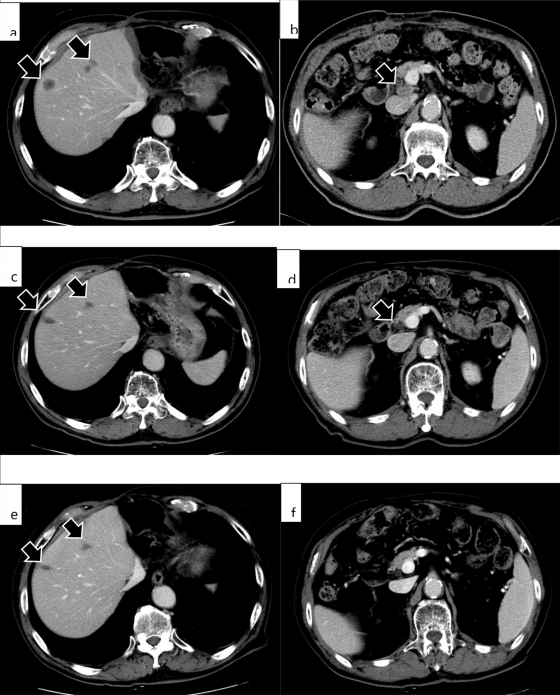

这名肝内胆管癌伴肝和淋巴结转移患者接受了帕博利珠单抗治疗。帕博利珠单抗给药四次(三周一次)后,CA19-9血清水平降至正常范围,CT显示转移性肝肿瘤和增大的肝门淋巴结明显变小。

但是,14次用药后出现躯干和四肢瘙痒和皮疹,并被诊断为大疱性类天疱疮。因此停止帕博利珠单抗治疗,开始对大疱性类天疱疮进行治疗。

腹部MRI显示第二次手术后4个月肿瘤复发;停止派姆单抗治疗9个月后复发病变未见变化(e,f)

令人意想不到的是,在停止治疗9个月后,患者仍然存活,没有肿瘤复发,这也意味着即使停用帕博利珠单抗治疗肝内胆管癌多发性转移后,该患者仍有持久的反应。